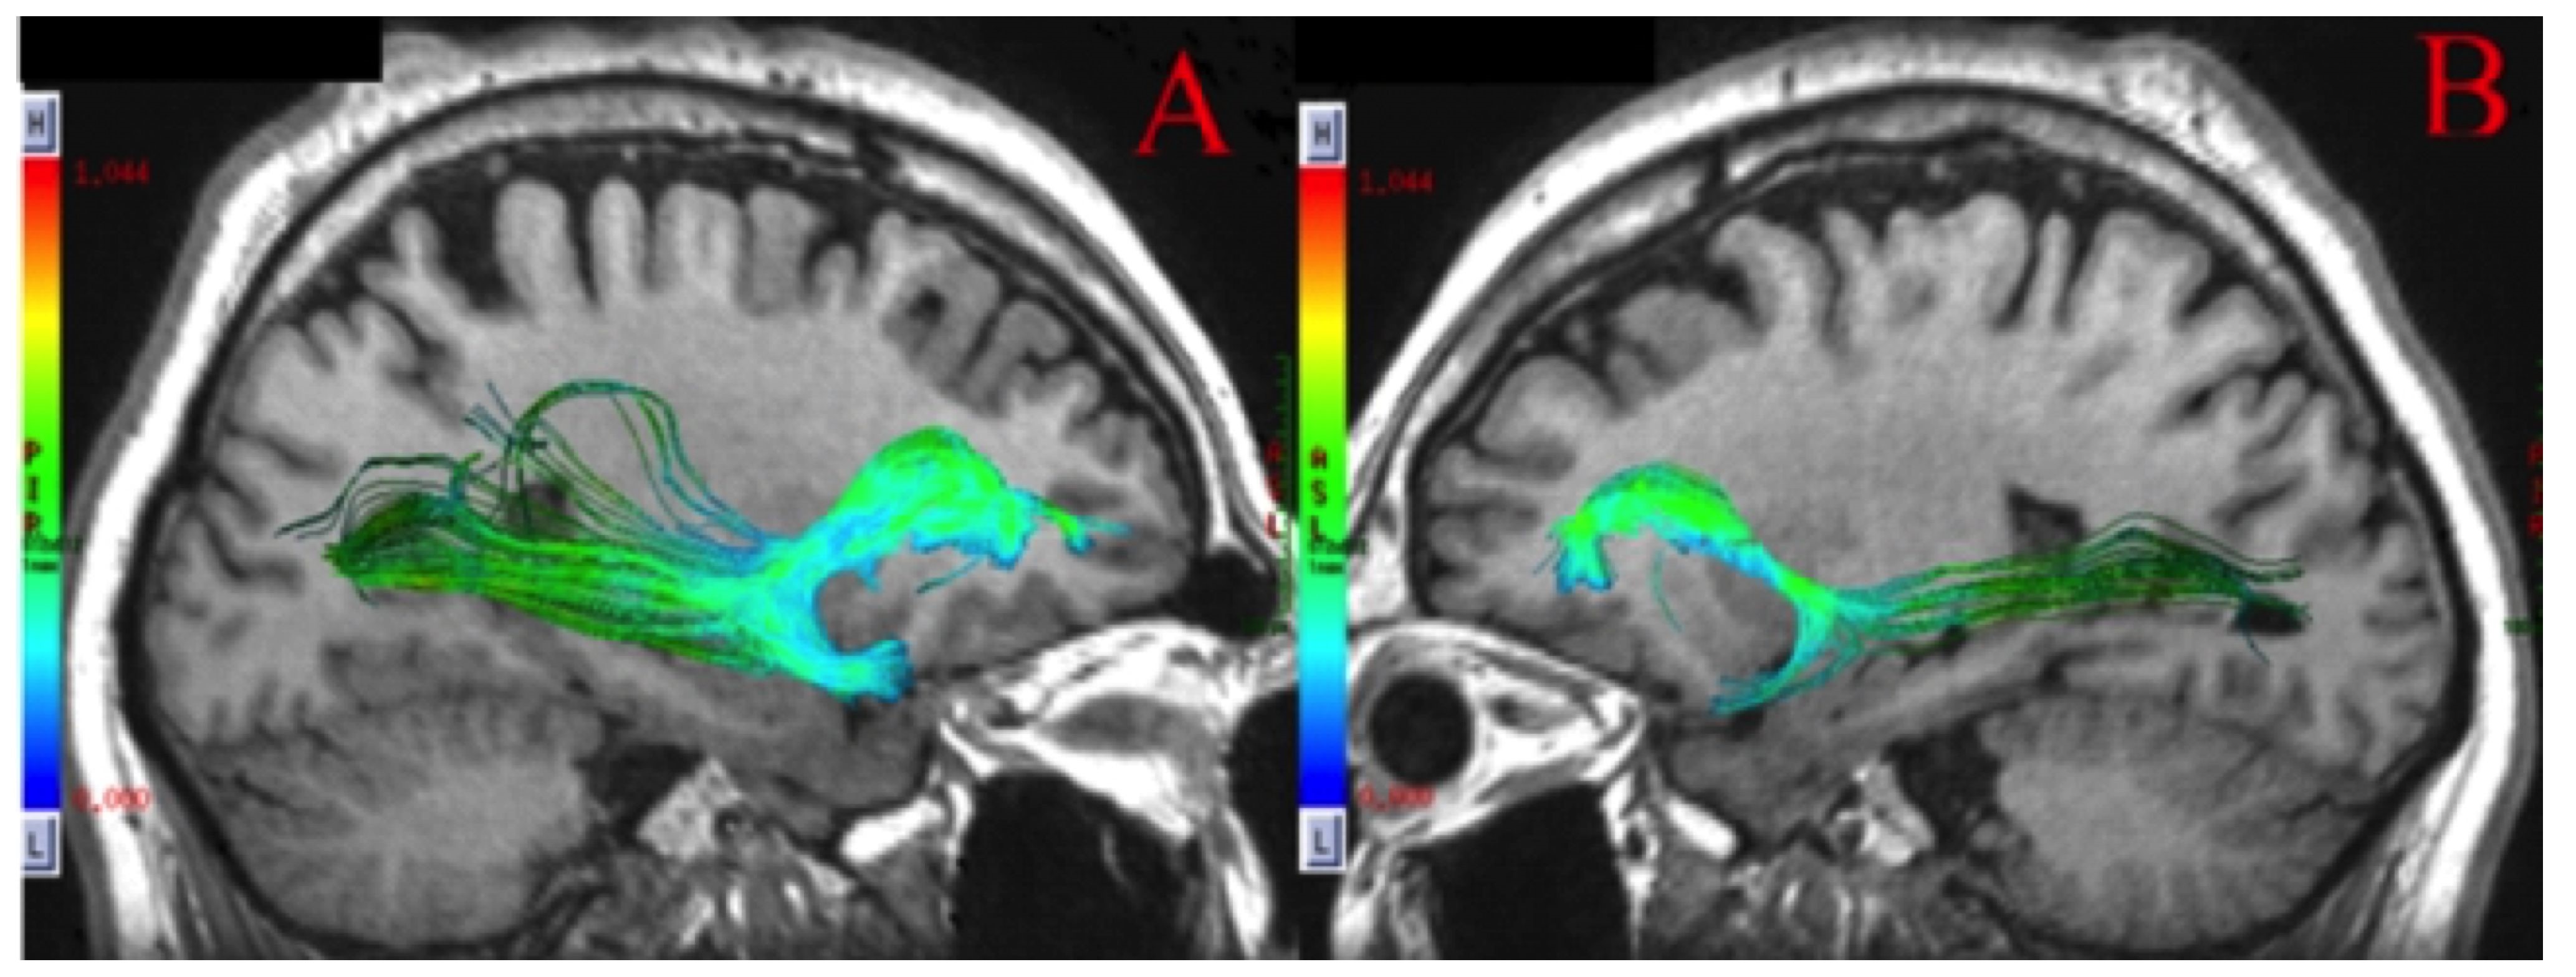

La tractografía es la única técnica no invasiva que permite la disección in vivo de las fibras de la sustancia blanca. Se trata de una técnica basada en difusión por tensor que cuantifica la magnitud y dirección del movimiento microscópico de las moléculas de agua. Es útil para detectar alteraciones en la microestructura de los fascículos de sustancia blanca, pudiendo observar de manera cualitativa la pérdida de continuidad de las fibras o la superposición de anisotropía, direccionalidad y conectividad (58). En epilepsia del lóbulo temporal se puede evaluar la vía visual y predecir la ocurrencia y extensión de defectos del campo visual posterior a resección temporal anterior, evaluando la extensión anterior del asa de Meyer dentro del polo temporal, donde se ha demostrado que longitudes menores a 35 mm del aspecto anterior del asa de Meyer, se asocia a defectos de los campos visuales posquirúrgicos (59), también se pueden evaluar las radiaciones ópticas pre y posquirúrgicamente y predecir la extensión del defecto de los campos visuales (60).

La tractografía puede demostrar reorganización estructural de los tractos asociados a memoria y lenguaje de acuerdo con la localización de la lesión y a la dominancia hemisférica; en pacientes con dominancia hemisférica izquierda y esclerosis temporal mesial ipsilateral se ha demostrado aumento de los tractos de sustancia blanca del hemisferio contralateral como resultado de reorganización funcional del lenguaje en regiones corticales contralaterales (61,62). La evaluación del fascículo arcuato que conecta las áreas receptivas y productivas del lenguaje ha demostrado ser mayor en el hemisferio dominante y esa asimetría se reduce cuando existe lesión en el hemisferio dominante secundaria a reorganización funcional (63,64), mientras que la evaluación del fascículo uncinado (Figura 7) y los datos de reorganización neuronal permiten predecir el desarrollo de afasia (65).

La resonancia magnética funcional en pacientes con epilepsia del lóbulo temporal secundaria a esclerosis temporal mesial permite delinear áreas del cerebro responsables de funciones específicas como áreas del lenguaje y memoria, identificando su localización anatómica para mejor planeamiento quirúrgico y anticipación de déficit cognitivos postquirúrgicos (47, 66). La lateralización de las funciones del lenguaje con resonancia magnética funcional presenta buena correlación con el test carotideo con amobarbital (Test de WADA) (67- 70). Pacientes con epilepsia del lóbulo temporal del lado izquierdo muestran activación bilateral o lateralización hemisférica derecha, o patrones atípicos de dominancia del lenguaje en relación con la reorganización en la representación del lenguaje (61,66,71). Utilizando áreas de comprensión lectora para activación del giro temporal superior(Figura 8)y tareas de fluencia verbal y generación de verbos para activación de giro frontal inferior, se logra lateralizar la función del lenguaje y ofrecer datos para mejor planeamiento quirúrgico de lesiones del hemisferio dominante (68,72,73).